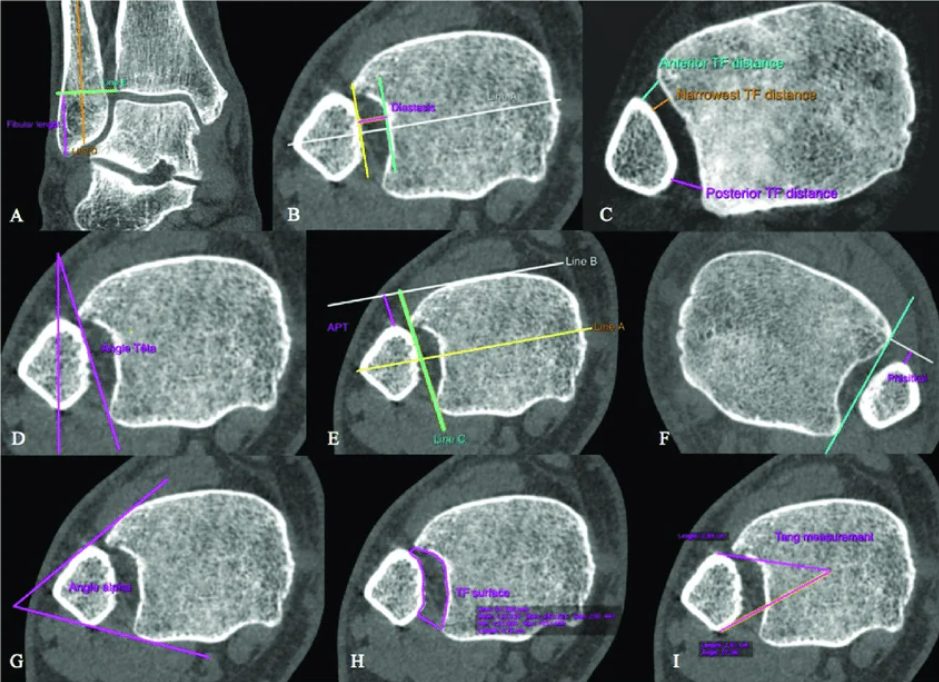

Рис. 13. Предложенные в литературе углы и дистанции для оценки синдесмоза

Стандартная рентгенография в прямой (AP) и ротационной (mortise) проекциях позволяет оценить три ключевых параметра межберцового синдесмоза:

Межберцовый светлый промежуток (tibiofibular clear space, TFCS) — измеряется на 1 см проксимальнее суставной поверхности большеберцовой кости. При интактном синдесмозе TFCS не должен превышать 6 мм.

Межберцовое перекрытие (tibiofibular overlap, TFO) — на прямой проекции должно составлять более 6 мм или более 42% ширины малоберцовой кости; на ротационной проекции — более 1 мм.

Медиальный светлый промежуток (medial clear space, MCS) — не должен превышать расстояние между куполом таранной кости и плафоном большеберцовой кости.

Рис. 14. Положение малоберцовой кости в боковой проекции

КТ превосходит стандартную рентгенографию в оценке целостности синдесмоза и способна выявлять подвывих синдесмоза, которую сложно визуализировать на обзорных рентгенограммах, особенно в неочевидных случаях. Возможность оценки обоих голеностопных суставов делает КТ предпочтительным неинвазивным методом оценки репозиции синдесмоза.

КТ-сканирование синдесмоза обычно проводится на уровне наиболее выступающей точки переднего бугорка большеберцовой кости. Повреждение синдесмоза диагностируется при межберцовом промежутке более 6 мм или расширении более 2 мм по сравнению с контралатеральной стороной. Повреждение с расхождением 2–3 мм может быть подтверждено на фронтальных КТ-срезах.

Рис. 15. Тибиофибулярная линия Гиффорда (TFL) на аксиальных срезах КТ и МРТ. Линия проводится вдоль переднелатеральной кортикальной поверхности малоберцовой кости. Расстояние от переднего бугорка Тилло-Шапута до TFL не должно превышать 2 мм. Параметр чувствителен к ротационной нестабильности.

КТ с нагрузкой (weight-bearing CT, WBCT) обладает дополнительным преимуществом — динамической оценкой синдесмоза: при нагрузке выявляются значимые латеральная трансляция и наружная ротация малоберцовой кости относительно вырезки.

В последние годы WBCT стала ведущим инструментом диагностики субклинической (subtle) нестабильности синдесмоза — той, которую не удаётся выявить стандартными методами. Наиболее перспективным направлением является трёхмерный волюметрический анализ: объёмные измерения синдесмоза на протяжении 5 см проксимальнее плафона большеберцовой кости продемонстрировали площадь под ROC-кривой 0,96 с чувствительностью 90% и специфичностью 95% (Ashkani Esfahani et al., 2022). Трёхмерное картирование расстояний (3D distance mapping) на WBCT показало наибольшую диагностическую точность в первых 1–3 см вырезки с AUC 80,9–83,0% (Krähenbühl et al., 2025). Эти данные свидетельствуют о том, что 3D-волюметрия на WBCT может стать новым стандартом диагностики повреждений синдесмоза, особенно в клинически неоднозначных ситуациях.